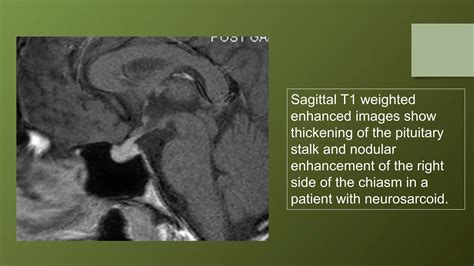

• Inflammation: Inflammation of the pituitary gland, known as hypophysitis, can be detected on an MRI scan. This condition can cause hormonal deficiencies and other symptoms.

• Pituitary Stalk Lesions: Lesions that affect the pituitary stalk, which connects the pituitary gland to the hypothalamus, can cause hormonal imbalances and other symptoms.